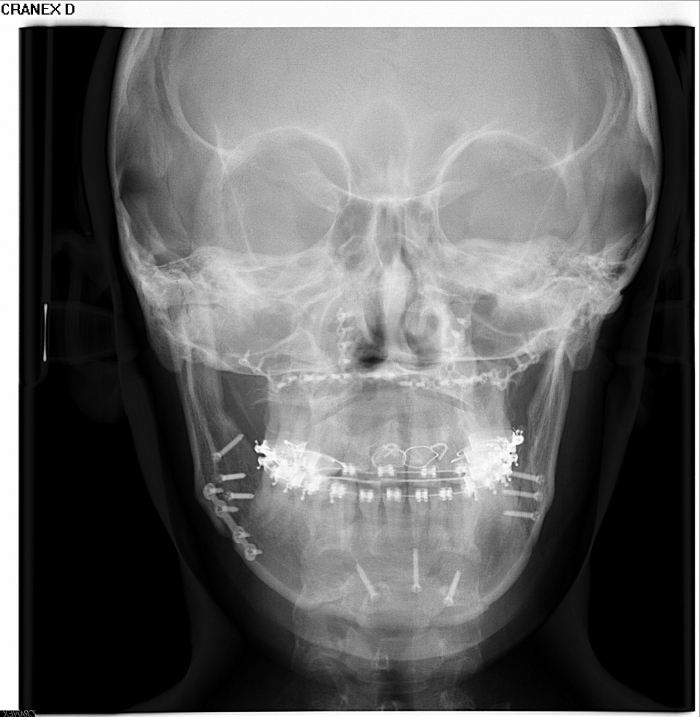

Telerradiografia Frontal após a cirurgia - Clínica Cliniface

Telerradiografia Frontal após a cirurgia